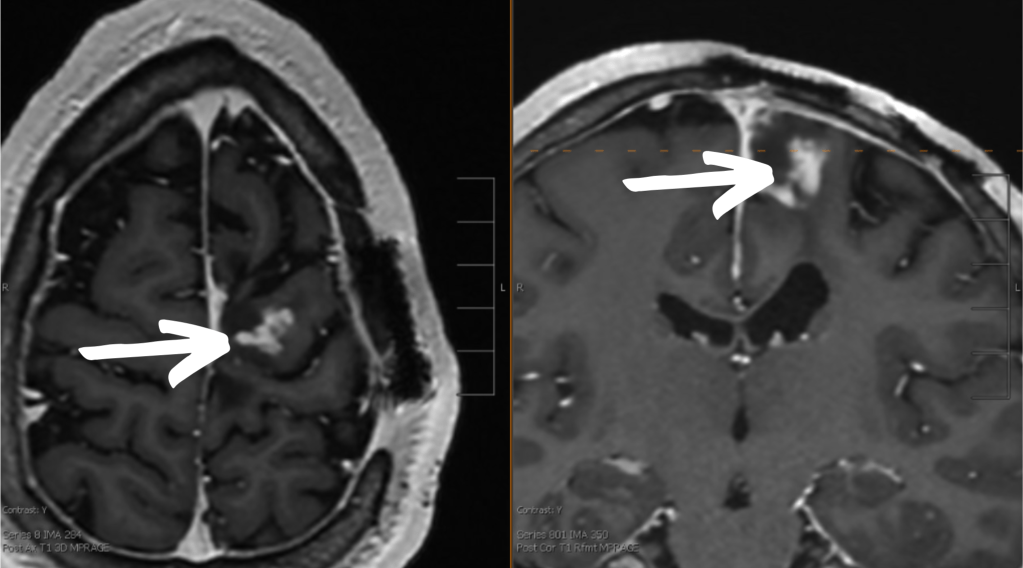

On February 4th I had my usual bimonthly MRI. We have been following my tumor closely because of an area of enhancement (tumor cells recruiting blood vessels) that has been on my scans for more than a year. I have been on Vorasidenib (the newest brain tumor treatment) since September 2023 to stop or at least slow down any tumor growth.

Unfortunately, the Voarsidenib isn’t slowing down the growth enough for this particular spot, so we have to change course.